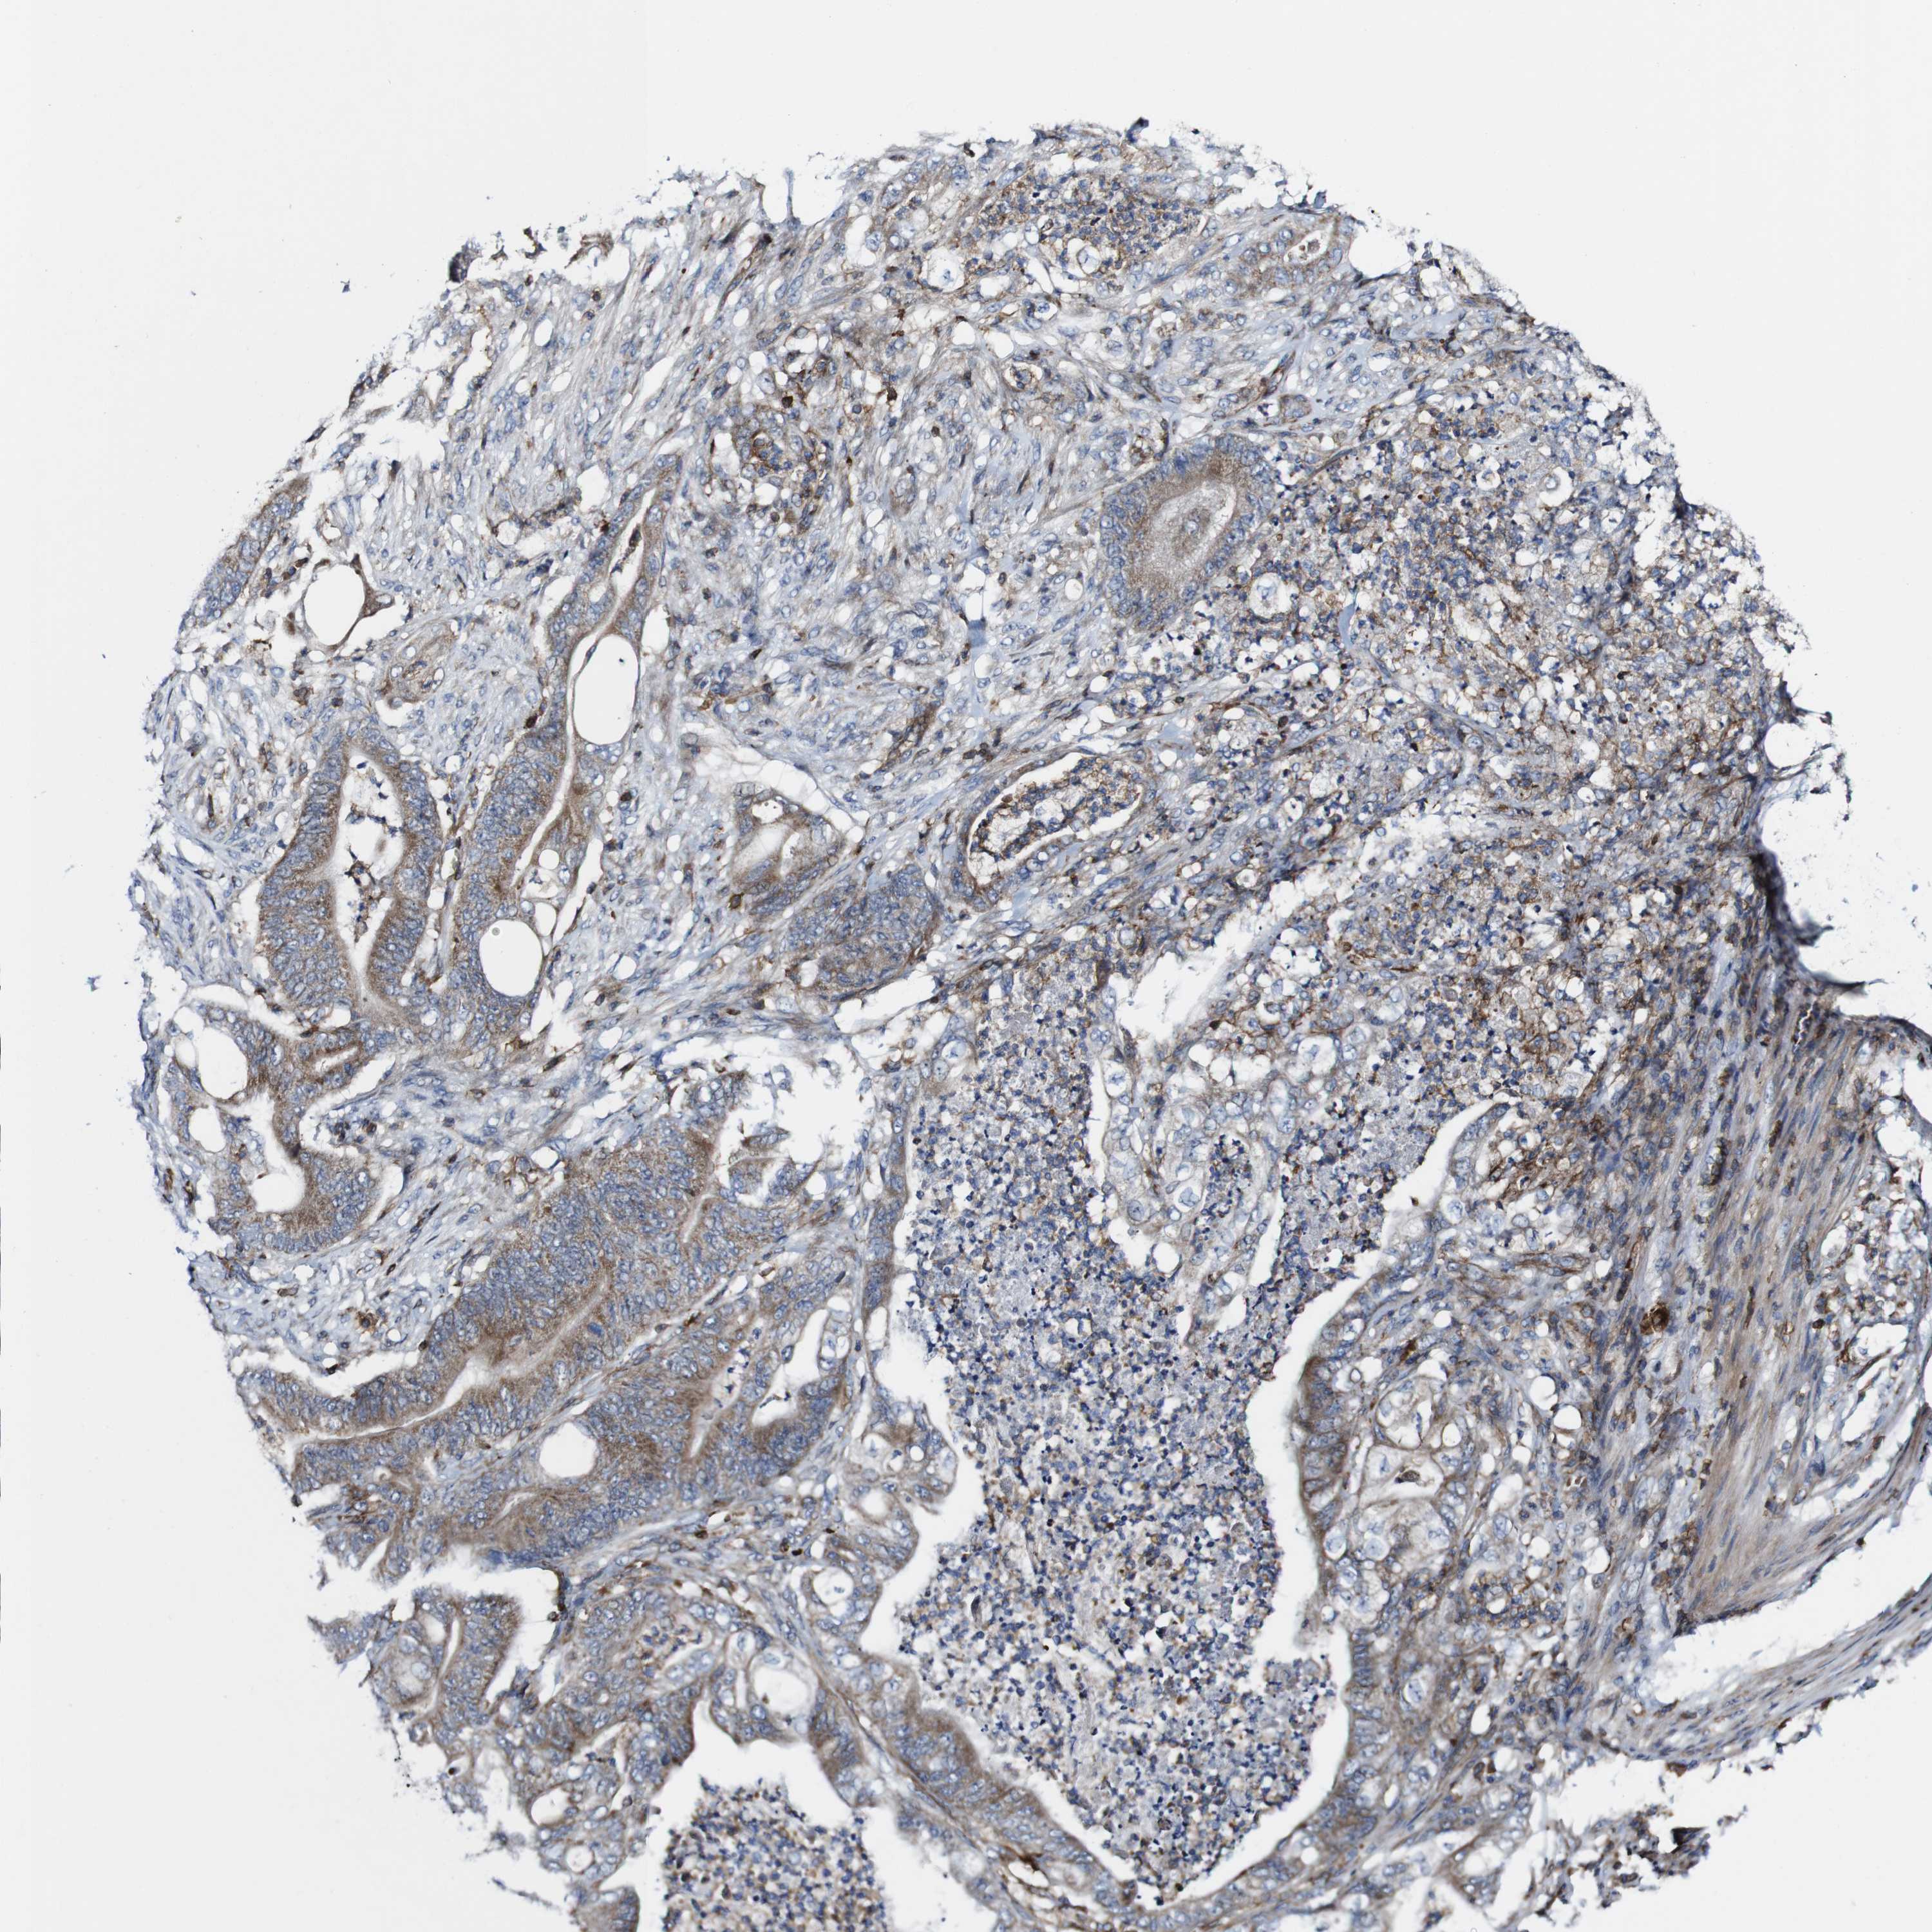

STOMACH CANCER - Protein expressioni

A mouse-over function shows sample information and annotation data. Click on an image to view it in a full screen mode. Samples can be filtered based on level of antibody staining by selecting one or several of the following categories: high, medium, low and not detected. The assay and annotation is described here.

Note that samples used for immunohistochemistry by the Human Protein Atlas do not correspond to samples in the TCGA dataset.

Antibody stainingi

Antibody staining in the annotated cell types in the current human tissue is reported as not detected, low, medium, or high, based on conventional immunohistochemistry profiling in selected tissues. This score is based on the combination of the staining intensity and fraction of stained cells.

Each image is clickable and will lead to virtual microscopy that enables deeper exploration of all samples and also displays staining intensity scores, fraction scores and subcellular localization as well as patient and tissue information for each sample.

Antibody HPA040820

Antibody CAB013089

Staining

High

Medium

Low

Not detected

Intensity

Strong

Moderate

Weak

Negative

Quantity

>75%

75%-25%

<25%

None

Location

Nuclear

Cytoplasmic/membranous

Cytoplasmic/membranous,nuclear

Adenocarcinoma, NOS